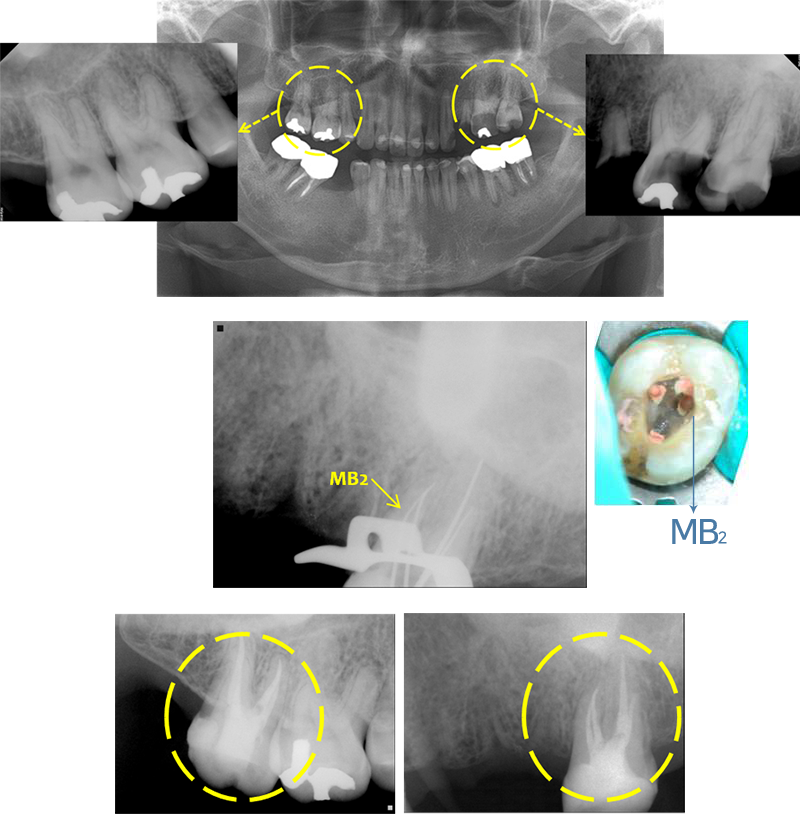

양측성으로 나타난 4개 근관 어금니의 신경치료 사례입니다.

양쪽 상악 대구치 모두 신경치료 필요할 정도로

충치 심한 상태로 서울에스치과에 내원하여 주셨습니다.

상악 대구치는 보통 기본적으로 MB, DB, P 신경관

3개까지 치료하는 경우가 일반적입니다.

MB2 라는 작은 신경관이 존재하기는 하지만 대부분의

실제 치료 과정상 발견하기는 어려운 신경관입니다.

서울에스치과에서는 모든 신경관을 발견하여 치료하여 재발을 방지하고

자연치아를 보존할 수 있는 치료를 진행하였습니다.